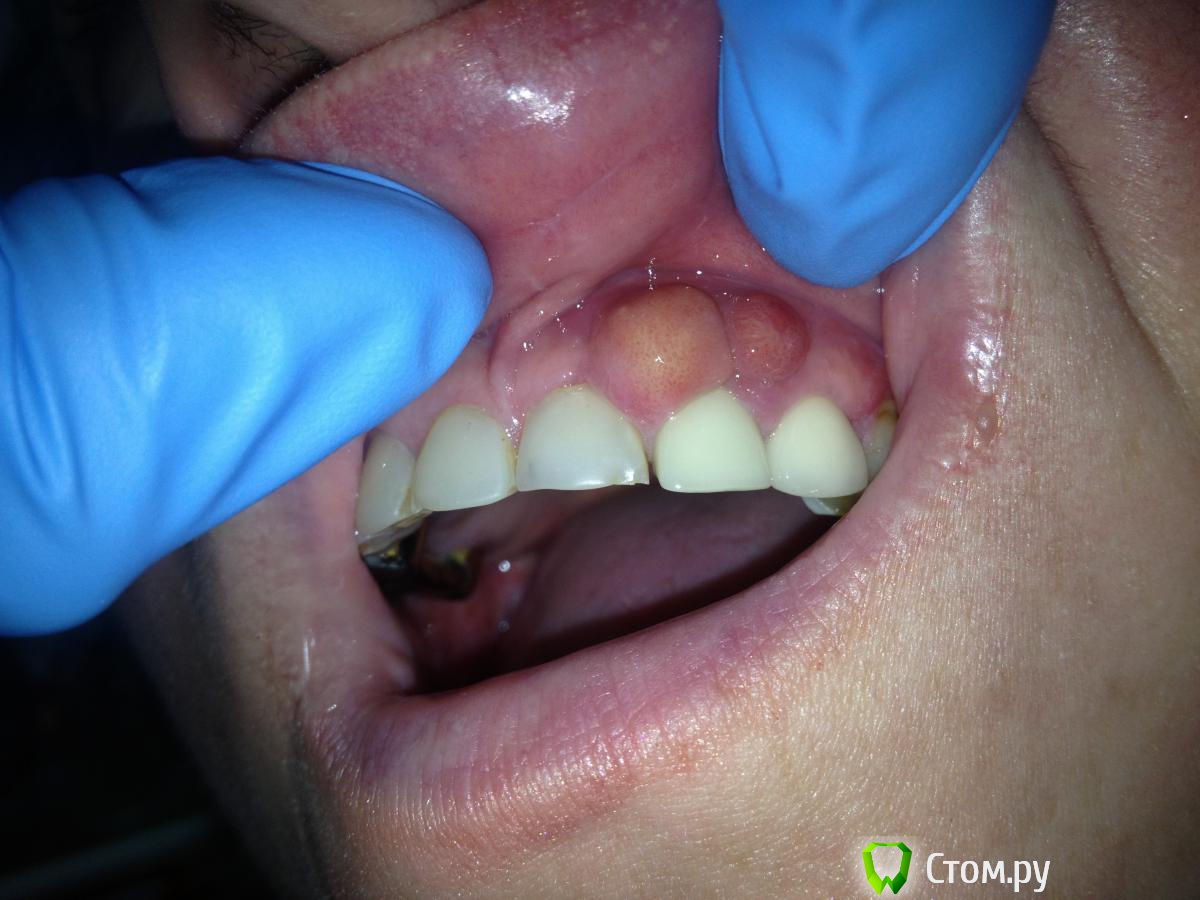

MaxDok Опубликовано 25 февраля, 2014 Поделиться Опубликовано 25 февраля, 2014 Пациент обратился с целью протезирования , жалоб не было , перкуссия в проекции 22 слабо положительная , говорит что укололся косточкой от рыбы . Ссылка на комментарий

Acidrocker Опубликовано 25 февраля, 2014 Поделиться Опубликовано 25 февраля, 2014 Эпулис? Пародонтальный абсцесс? Ссылка на комментарий

Солнечный СВЕТ Опубликовано 26 февраля, 2014 Поделиться Опубликовано 26 февраля, 2014 (изменено) Макс Size L перчи огонь))) надо резать в пределах здоровых тканей,моя версия что это эпулис. Изменено 26 февраля, 2014 пользователем Солнечный СВЕТ Ссылка на комментарий

red_butler Опубликовано 27 февраля, 2014 Поделиться Опубликовано 27 февраля, 2014 Тоже думаю за эпулис, гиста расставит все точки... резать Ссылка на комментарий

MaxDok Опубликовано 27 февраля, 2014 Автор Поделиться Опубликовано 27 февраля, 2014 Эпулис? Пародонтальный абсцесс? Сам думаю что эпулис .Завтра пациент назначен , будем резать , и на гистологию если приидется . А консистенция какая? Очень плотная . У меня все реже с подобным приходят, вот когда в госе работал, бывали, особенно из-под штамповок Тут из под металлоХерамики,тоже самое. Ссылка на комментарий